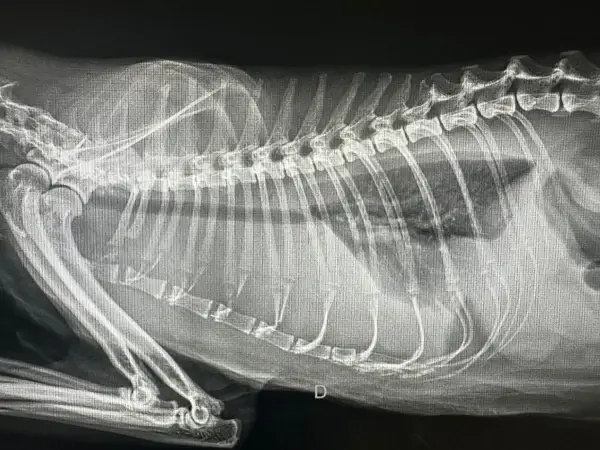

Diagnóstico por Imagen: Radiología y Ecografía

El diagnóstico por imagen es fundamental en medicina felina moderna. Muchas enfermedades solo pueden diagnosticarse mediante visualización directa de órganos internos, y la capacidad de obtener imágenes de alta calidad determina la precisión del diagnóstico.

Radiología digital: Nuestro equipo de rayos X digital proporciona imágenes de alta resolución en segundos, con una fracción de la radiación de los sistemas analógicos tradicionales. Esto es especialmente importante en gatos, donde la exposición debe minimizarse por su menor tamaño corporal.

La radiografía es insustituible para:

- Detección de fracturas, displasias y artropatías

- Localización de cuerpos extraños radiopacos

- Evaluación de patología abdominal (obstrucción intestinal, organomegalia)

Realizamos estudios radiográficos con sedación mínima o sin sedación cuando es posible, priorizando el bienestar del paciente. En casos donde se requieren múltiples proyecciones o posiciones específicas, utilizamos sedación leve para evitar estrés y garantizar la calidad de las imágenes.

Traumatismos: Caídas desde altura (síndrome del gato paracaidista), atropellos o ataques de otros animales. Realizamos evaluación completa del paciente, radiografías de cuerpo entero, estabilización hemodinámica y cirugía urgente si es necesario.